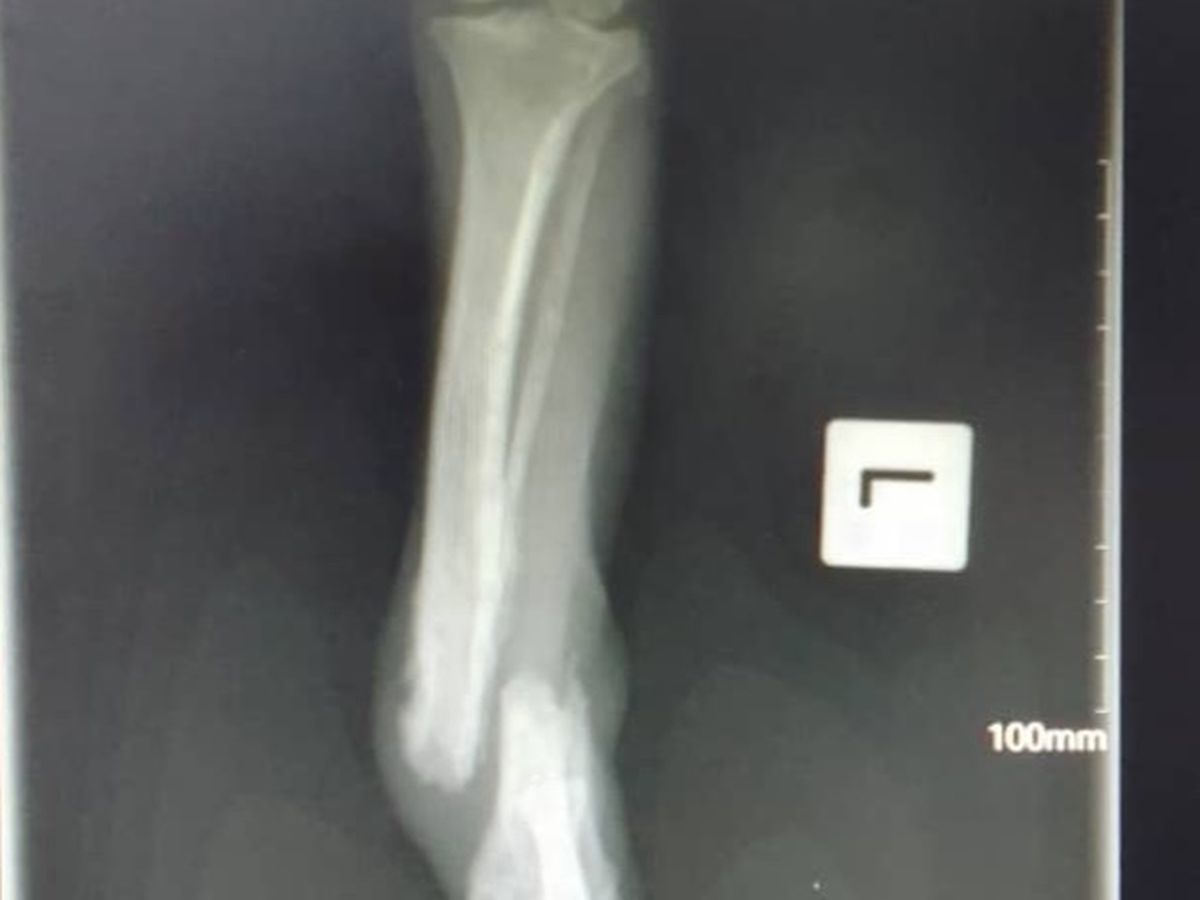

Hi, I am one of the vets at the RSPCA PNG and I am helping to fundraise for a new xray machine as ours broke recently. Unfortunately, dogs getting run over by cars is a daily occurrence here in Papua New Guinea. If we are lucky we can fix a fracture, or even amputate a leg but still save an animal's life. Other times the injuries are so severe that humane euthanasia is the kindest thing to do. Not having an xray machine is like flying blind and a lot of animals that could be saved are put to sleep or go through unnecessary suffering as we can make the wrong choice. You can help prevent this by helping us fundraise for an xray machine.